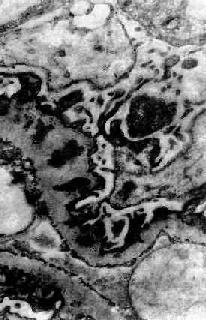

图12-18 膜性肾小球肾炎

电镜下见肾小球毛细血管基底膜表面,上皮细胞下电子致密沉积物,基底膜向表面突出伸入沉积物之间,上皮细胞足突融合